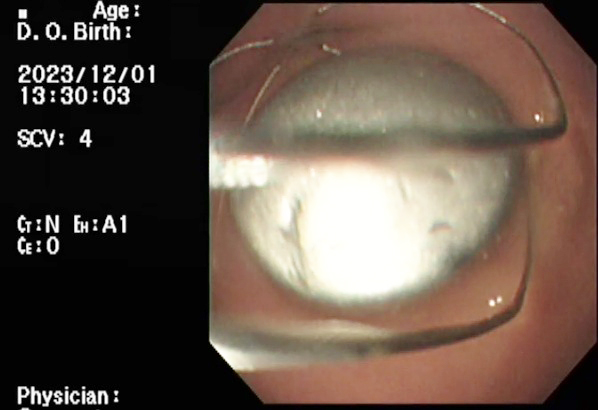

下の写真は、バスケット鉗子を用いてボタンを確保したところです。

バスケット鉗子が写りこんでいます

無事、摘出することができました。